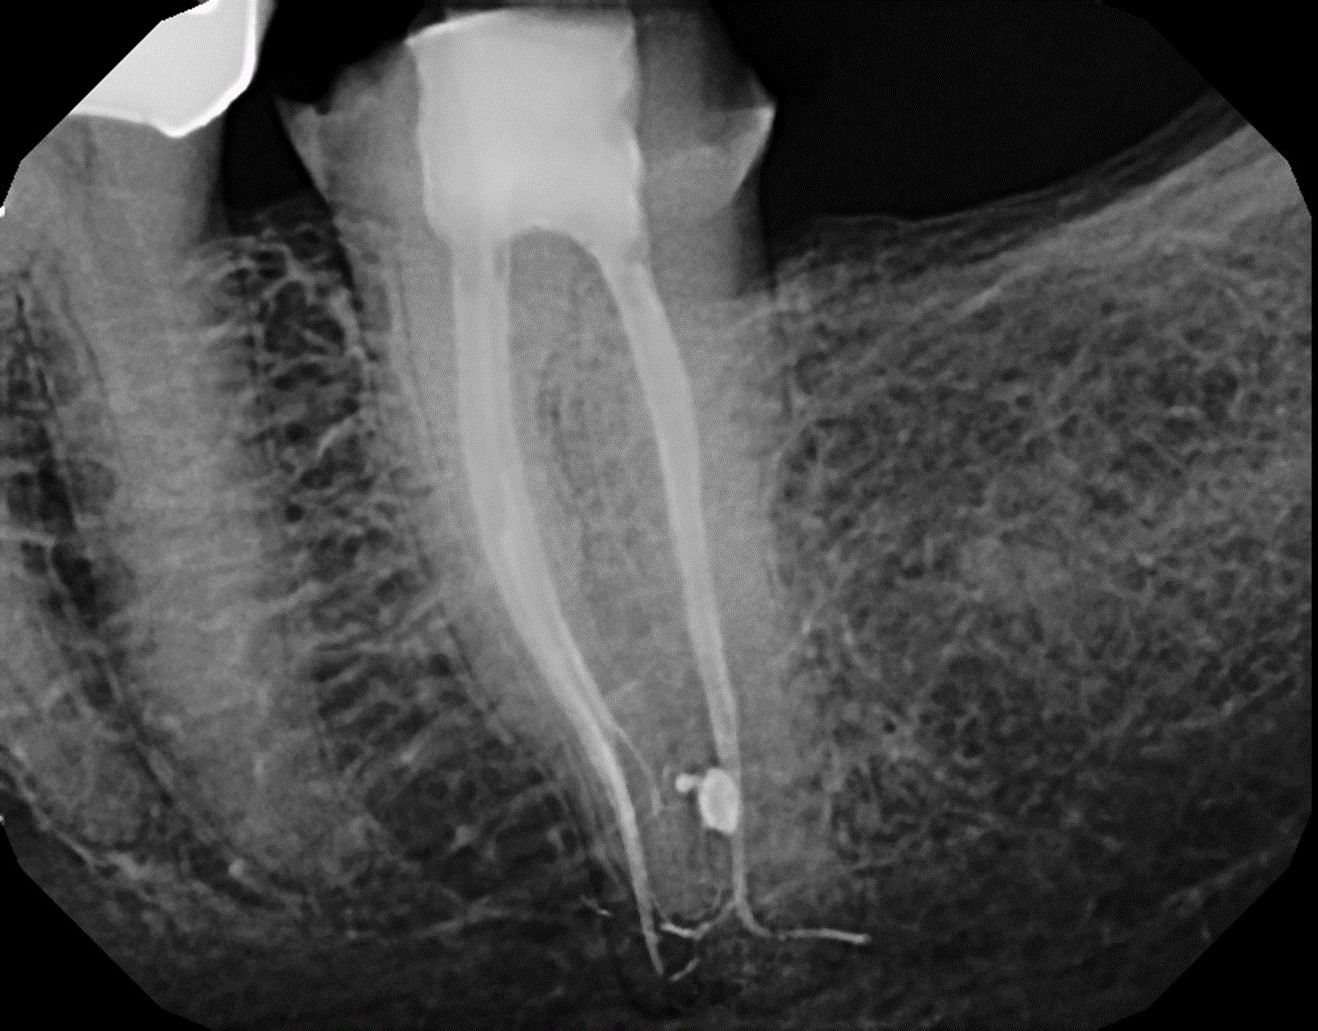

Fig 15. Postoperative obturation radiographs after multisonic ultracleaning technology, revealing complex and intricate canal anatomy.

Figure 15

With this technology, gentle vortical flow is induced within the root canal system with a slight negative pressure at the apices, which reduces the potential for extrusion. The result is a more complete removal of pulp tissue, bacteria, and bacterial biofilm within the root canal, including debris in anatomically complex structures (eg, isthmi, lateral canals, multiple apical foramina).18-20 In other words, it can clean and disinfect even where a file or rotary instrument cannot reach (Figure 15 through Figure 18). All this is accomplished with minimal instrumentation, most of the time to a size as small as a .04 taper #15 or #20 rotary instrument. In addition, conservation of root dentin results in a stronger root, which may increase the survival rate of the treated tooth.7